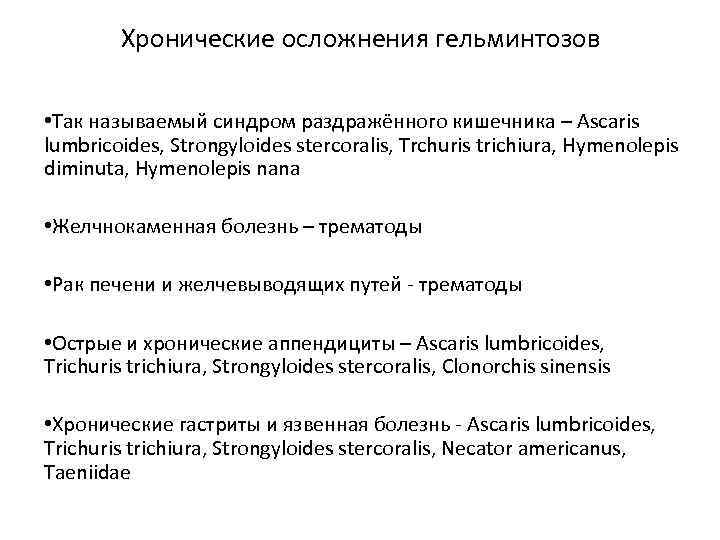

Хронические осложнения гельминтозов • Так называемый синдром раздражённого кишечника – Ascaris lumbricoides, Strongyloides stercoralis, Trchuris trichiura, Hymenolepis diminuta, Hymenolepis nana • Желчнокаменная болезнь – трематоды • Рак печени и желчевыводящих путей - трематоды • Острые и хронические аппендициты – Ascaris lumbricoides, Trichuris trichiura, Strongyloides stercoralis, Clonorchis sinensis • Хронические гастриты и язвенная болезнь - Ascaris lumbricoides, Trichuris trichiura, Strongyloides stercoralis, Necator americanus, Taeniidae